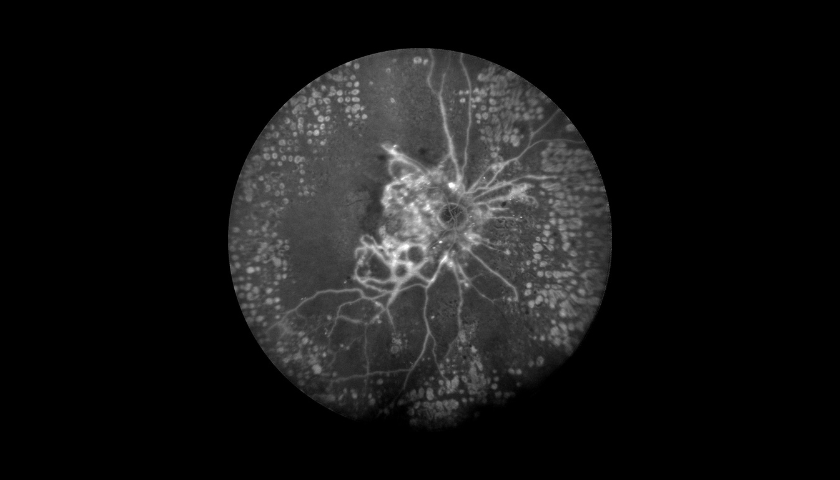

A Angiografia Fluoresceínica (AF) é um exame auxiliar de diagnóstico e monitorização em oftalmologia que permite visualizar e analisar a circulação da retina, com o objetivo de identificar possíveis alterações ou lesões que expliquem um determinado quadro clínico.

A Angiografia é indicada principalmente em patologias como a Retinopatia Diabética (RD), a Degenerescência da Idade (DMI), as oclusões vasculares (tromboses) e os tumores oculares. Utilizando o Spectralis® HRA+OCT (com as lentes de 30o, 55o ou 102o), é um procedimento de diagnóstico no qual uma sequência rápida de fotografias é tirada após injeção de um corante para documentar a circulação sanguínea da Retina e também da Coróide e assim ajudar a diagnosticar e tratar muitas doenças oculares.